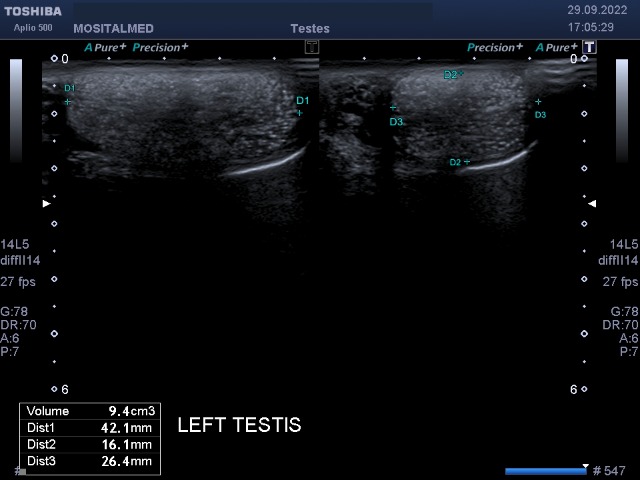

Редкий случай, коллеги.

Сплошные микролиты в ткани обоих яичек.

Я впервые встретил такой тотальный микролитиаз.